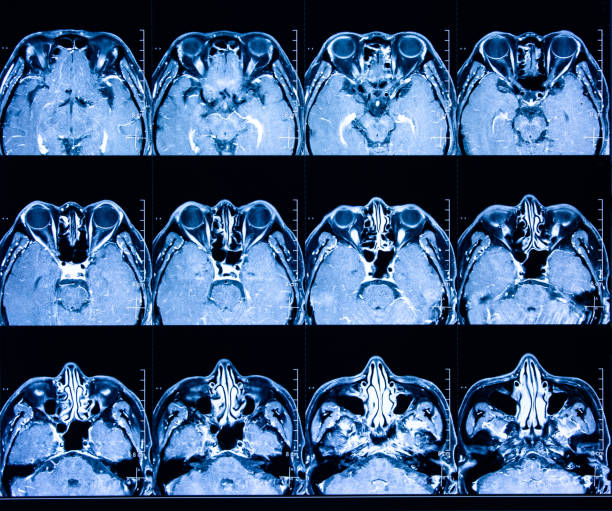

為了描述目的,患者按入組順序被賦予編號,并被連續分配到三組中的一組,每組三名。根據模型2分割,ICH體積范圍為0.1至54.9mL(平均ICH體積為23.5mL)。5名ICH患者受累于局限性腦葉,其余患者受累于基底神經(jīng)節或外囊深處。3名患者的ICH位于丘腦(圖1),1名患者的血腫位于多個(gè)腦結構(即尾狀核、殼核和蒼白球)。平均而言,MSCs是在ICH后3天注射的。